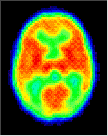

The high CMRGlc during 3 to 10 years corresponds to the period of exuberant connectivity in humans and is probably required to meet the energy demands of the neuronal processes and synapses that are also in excess by about a factor of two compared to adults. Shown above are PET scans from 3 different ages showing the relative glucose metabolic rate. Beneath the PET scans are drawings showing the relative complexity of the dendritic structure of cortical neurons. The progressive increase in glucose utilization seen in development is consistent with anatomical studies showing an expansion of dendritic fields (and synaptic connectivity) and an increase in capillary density in the human frontal cortex during the same period. Thus, it is possible that the decrease in glucose metabolic rate in the adult reflects a "pruning" of excessive neuronal connectivity and a selective stabilization of the remaining neuronal connections.